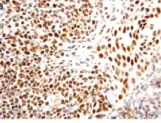

| Micrograph showing cutaneous T-cell lymphoma. H&E stain | |